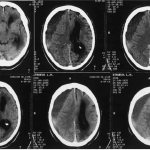

Depression during pregnancy , or depression before birth, is a mood disorder similar to clinical depression . Mood disorders are biological disorders that involve changes in brain . During pregnancy, hormonal changes can affect chemicals in the brain that are directly linked to depression and anxiety. They can be aggravated by difficult life situations, which can lead to depression in a woman even during pregnancy .